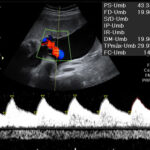

Imágenes

En LATIVA, nos especializamos en diagnósticos precisos y manejo integral para la salud de la madre y el bebé. Nuestro equipo de subespecialistas certificados utiliza tecnología de vanguardia para ofrecerles tranquilidad y el mejor cuidado posible en cada etapa.